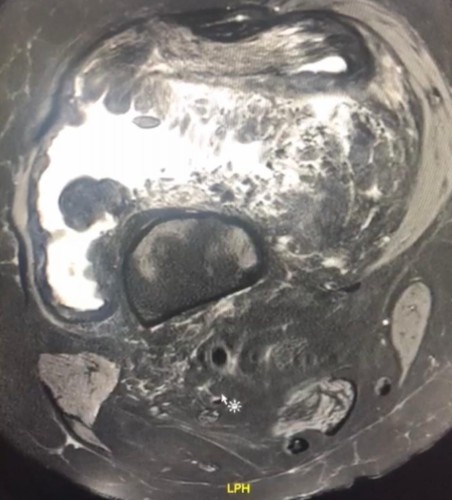

أعلنت صحة المدينة المنورة عن بدء العمل في غرفة العمليات الجراحية المتخصصة لحالات أورام العظام والعضلات في مستشفى المدينة المنورة، حيث تمكّن فريق طبي في مستشفى المدينة المنورة من إجراء عملية استئصال ورم في الركبة اليمنى لمريضة في الستين من عمرها بعد معاناة أستمرت عدة أعوام، وقد تكللت العملية بالنجاح – ولله الحمد -.